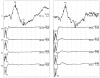

Results: Simultaneous recording of cortical and spinal EPs was obtained in > 80% of the trials. The EP responses increased with the intensity of the electrical stimulation, were reproducible overtime, and were blocked by application of Lidocaine jelly at the site of stimulation. The morphology (N1/P1), mean ± SD for latency (spinal N1, 4.6 ± 0.4 ms; P1, 6.8 ± 0.5 ms; cortical N1, 136.1 ± 4.2 ms; P1, 233.6 ± 12.8 ms) and amplitude (N1/P1, spinal, 38 ± 7 μV; cortical 19 ± 3 μV) data for the EP responses were consistent with those in the published literature. Reliable and reproducible EP recordings were obtained with the attachment of the electrodes to the rectal mucosa at predetermined locations between 16 and 8 cm above the anal verge, and the distance between the attachment sites of the electrodes (the optimal distance being approximately 3.0 cm between the two electrodes).